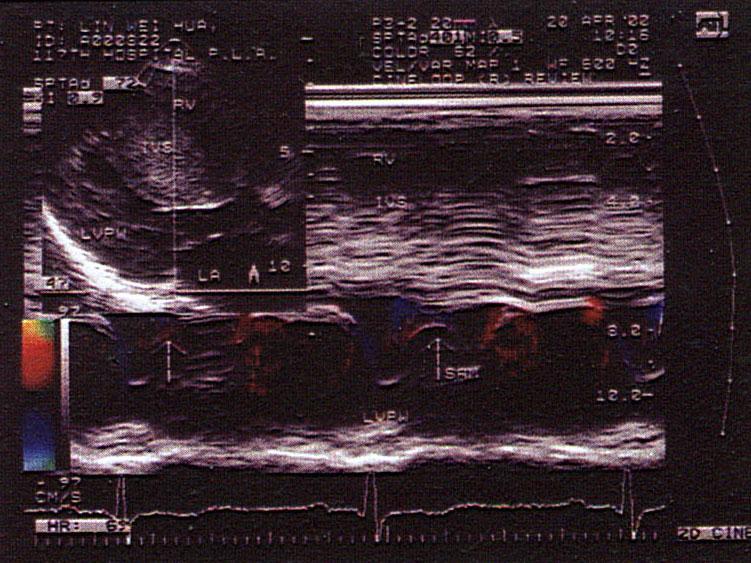

问题 该病例最可能的诊断?(?)

选项 A.高血压病 B.肥厚型心肌病 C.主动脉瓣狭窄 D.肌型主动脉瓣瓣下狭窄 E.限制性心肌病

答案 B